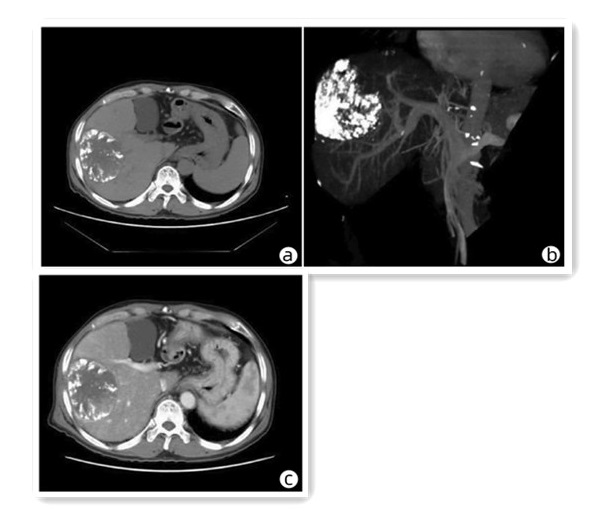

先天性左肝缺如合并肝细胞癌1例报告

王海林, 李敬东, 武国

2023, 39(6): 1408-1410. DOI: 10.3969/j.issn.1001-5256.2023.06.023

摘要(825) HTML (191) PDF (2003KB)(56)

摘要: